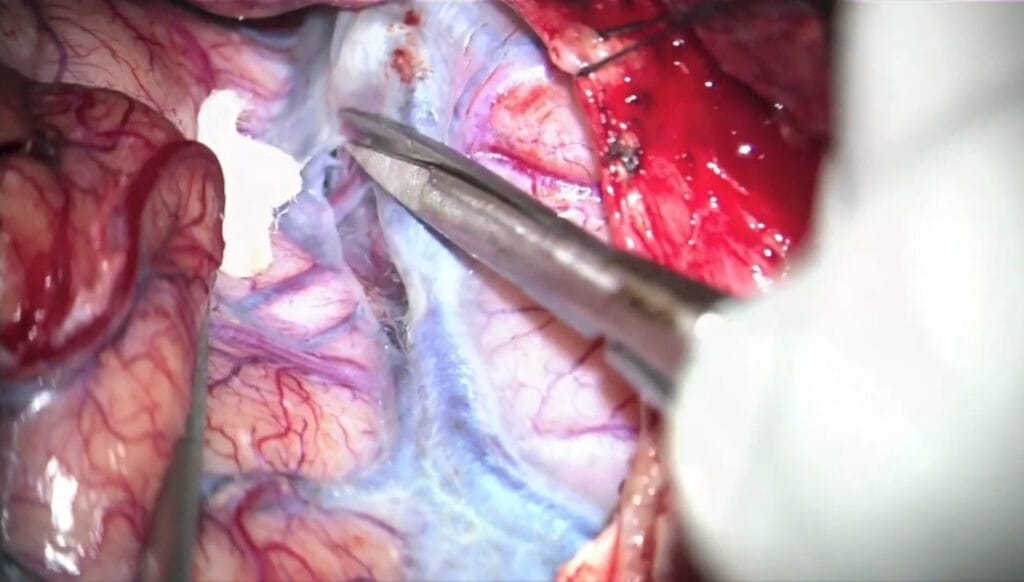

Aneurisma de la arteria hipofisaria superior – Clinoidectomía Intradural

El Dr. Javier Ibáñez realiza una clinoidectomía intradural y apertura de los anillos durales para abordar un aneurisma hipofisario superior.